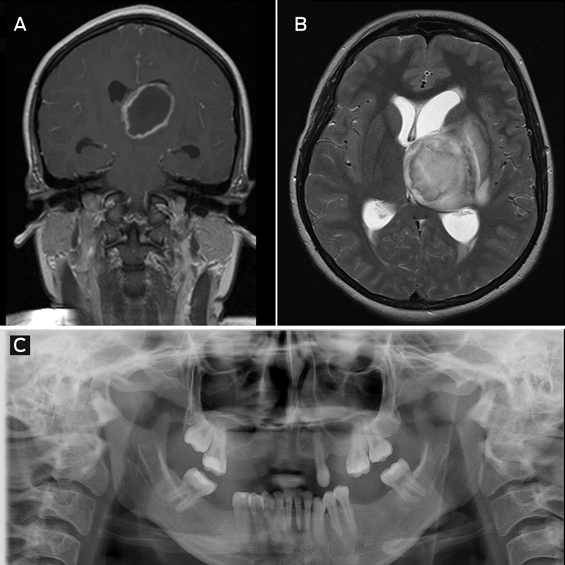

Magnetic resonance imaging showed a 4.6 × 5.1 cm ring-enhancing lesion in the left thalamus, with extensive surrounding oedema (Figure, A and B).

Microscopy of a biopsy sample showed pus and gram-positive cocci. Cultures grew Streptococcus anginosus (also known as Streptococcus milleri), an organism that is part of normal oral flora and a well known cause of metastatic abscesses.

The patient admitted to undergoing multiple recent tooth extractions (Figure, C). She was treated with 6 weeks of intravenous benzylpenicillin and made a full recovery, with complete abscess resolution on follow-up imaging.